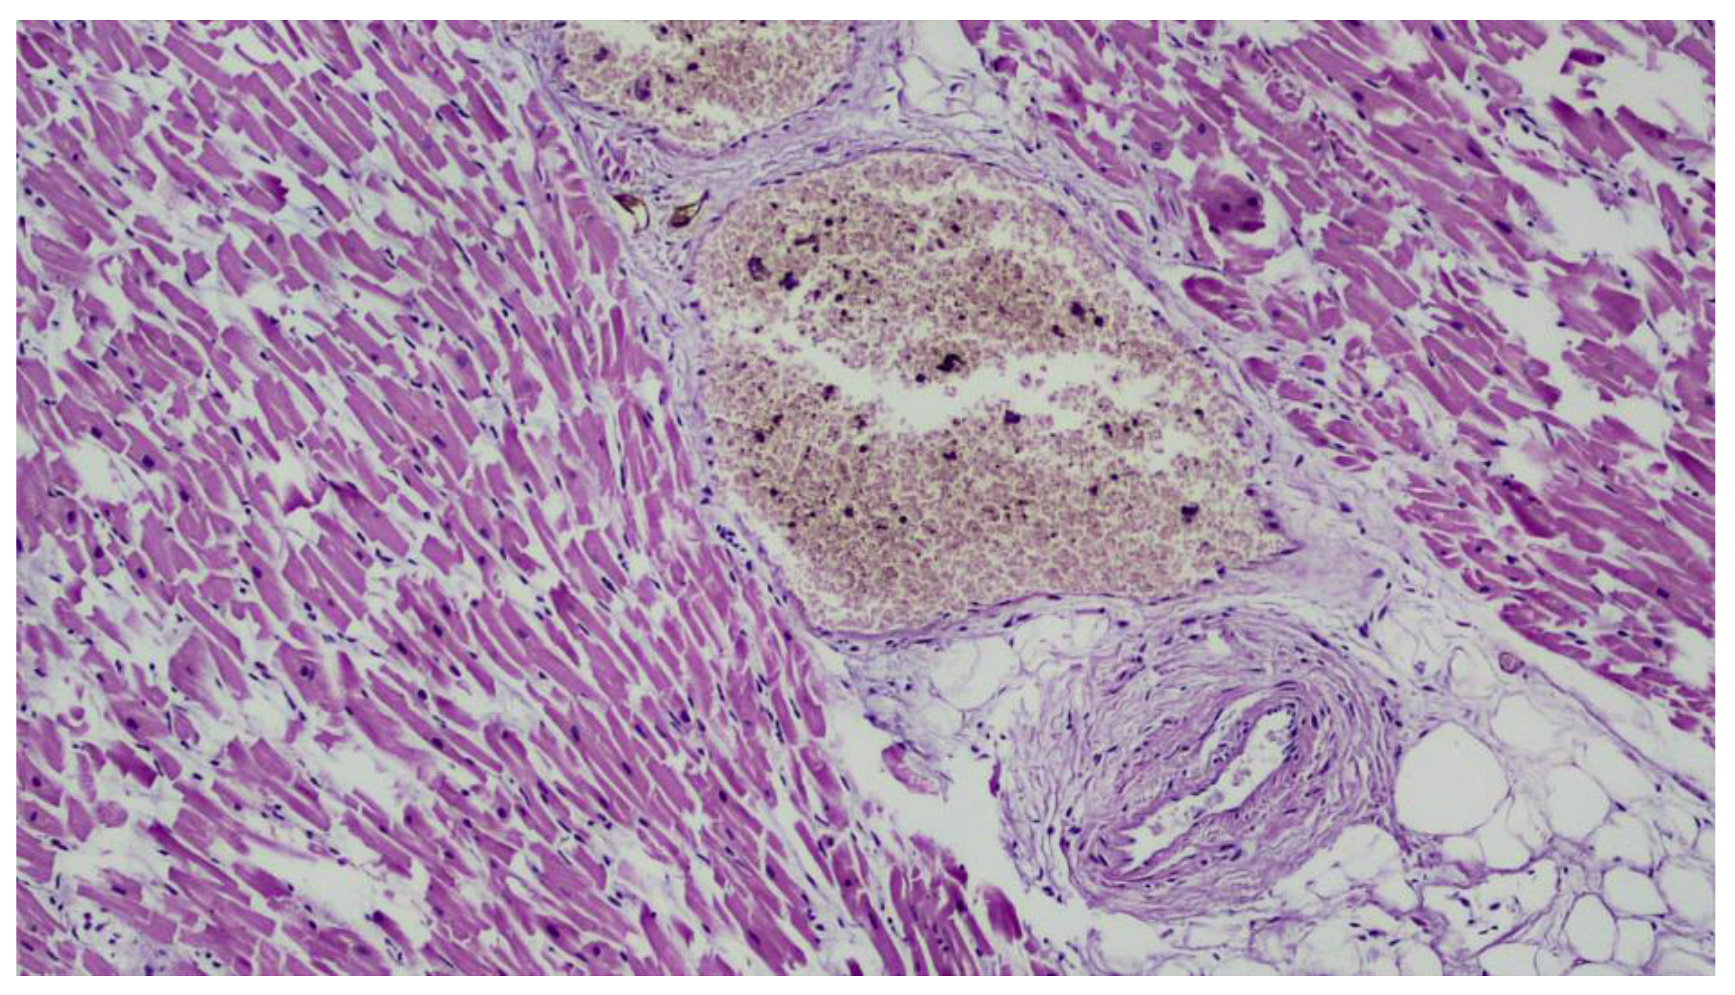

2. Case Presentation